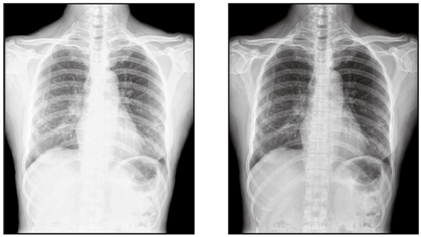

DICOM是人眼所看到的實際亮度,在電腦螢幕上用明顯的灰階呈現出來,讓X光片的顯影能夠更清晰。Wincomm提供的DICOM功能,設計概念以方便操呈現作為出發點,並提供三種色溫,符合不同地區的喜好選擇。此外特別設計亮度鎖定功能,以保證DICOM模式下,亮度的準確性。

Picture: General screen VS DICOM

Picture: Three kinds color temperatures modes